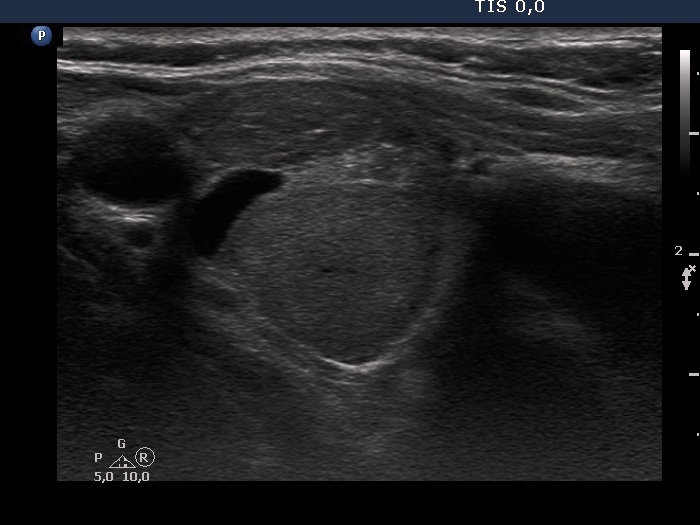

Consecutive patients with the final diagnosis of Hashimoto's thyroiditis - case 37 (239) (ultrasonographic picture 2)

Right lobe, another transverse view.